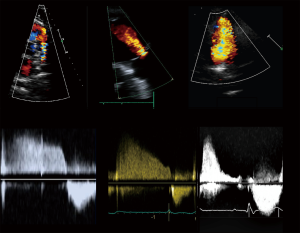

Current guidelines (4,8) recommend a standardized echocardiographic protocol in TOF patients. The precise evaluation of PR—a universal finding—and the main driver of RV dilatation and dysfunction, is essential. Theoretically, PR may be quantified with the same methods as aortic regurgitation. Proposed values for severe regurgitation include an effective regurgitant orifice area (EROA) greater than 115 mm2, regurgitant volume >115 mL, pressure half time <100 ms, a PR index <0.77, jet width >65% of the right ventricular outflow tract (RVOT) width, and diastolic flow reversal in PA branches (Figure 2) (11); however, these values are not robust and in clinical practice there is no widespread accepted method for quantifying PR with TTE. Furthermore, RV dilatation, the functional consequence of PR, is sensible but not specific for severe PR (12). For these reasons, grading PR severity by TTE remains challenging. Furthermore, while PR is the most common valvulopathy, other frequent findings are functional tricuspid regurgitation, aortic regurgitation, and residual pulmonary or subpulmonary stenosis.